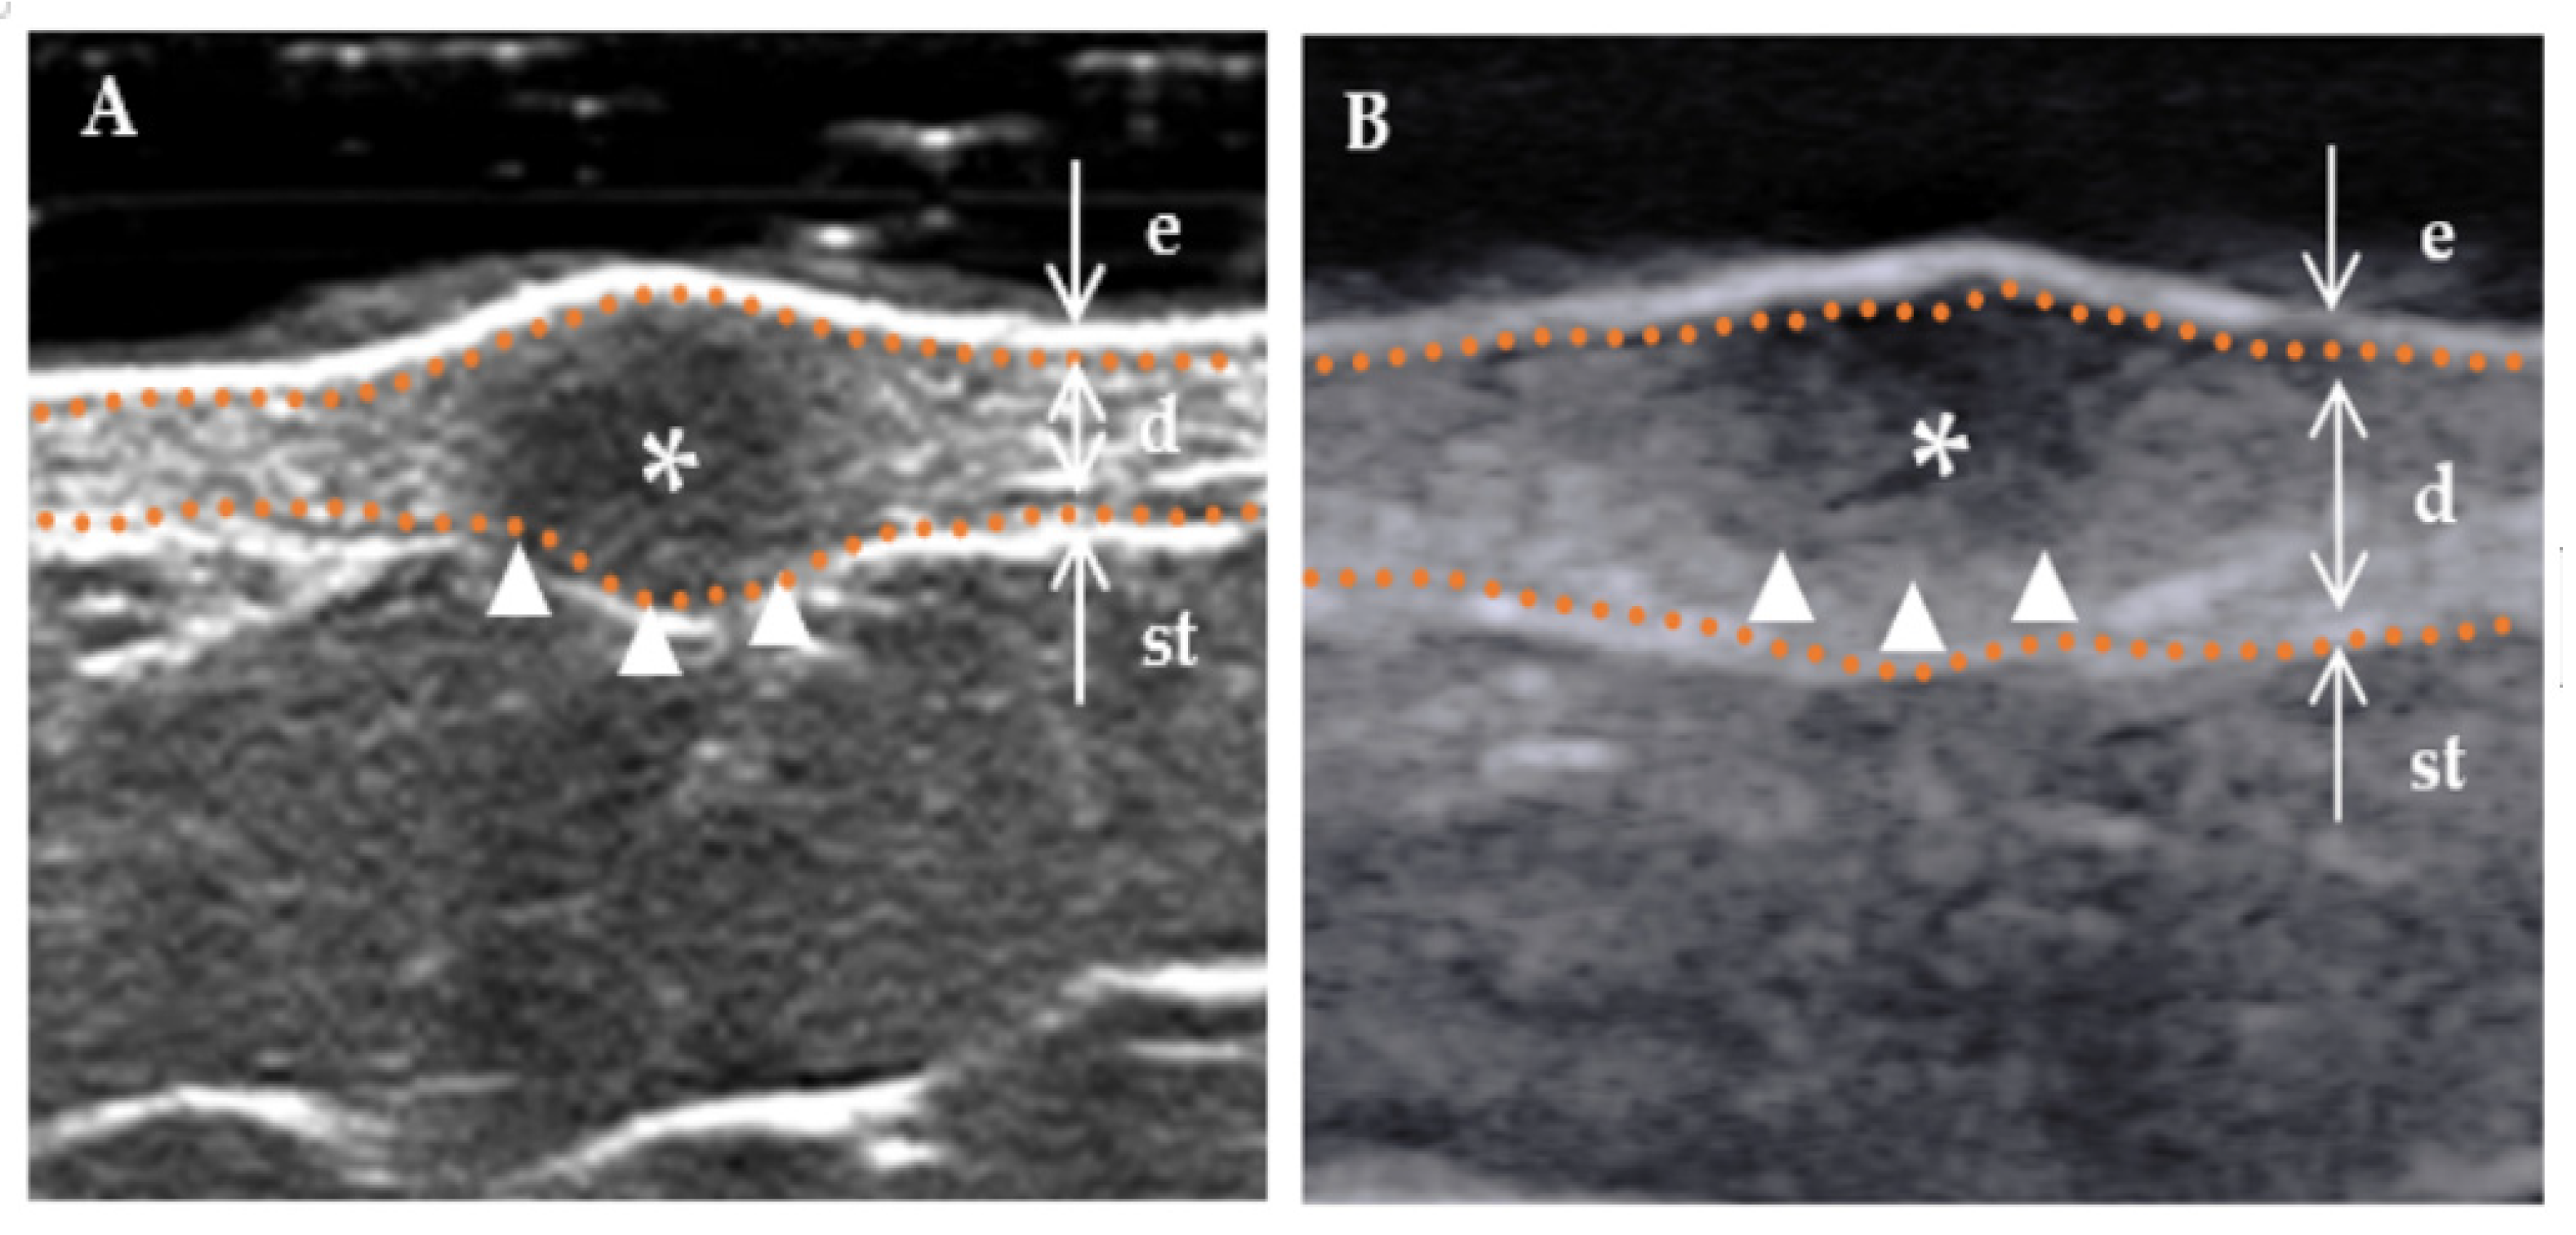

| shape, n (%) | 0.001 * | ||

| Regular (incl. creeping) | 5 (29.4%) | 26 (78.8%) | |

| Irregularity | 12 (70.6%) | 7 (21.2%) | |

| Internal echogenicity, n (%) | 0.004 * | ||

| Homogenous | 4 (23.5%) | 27 (81.8%) | |

| Heterogenous | 13 (76.5%) | 6 (21.2%) | |

| Stratum basal, n (%) | 0.002 * | ||

| Dermis | 6 (35.3%) | 26 (78.8%) | |

| Subcutaneous | 11 (64.7%) | 7 (21.2%) | |